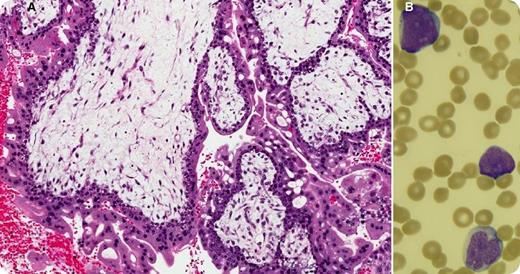

Thirteen months after the successful treatment of a persistent complete hydatidiform mole (panel A: diffusely hydropic, grape-like chorionic villi surrounded by hyperplastic atypical trophoblast), a 27-year-old woman with no family history of cancer presented with fatigue, sore throat, and petechiae for a few weeks. Her prior treatment included a single cycle of single-agent methotrexate that was followed, because of a further increase in human chorionic gonadotropin, by 9 biweekly cycles of etoposide, methotrexate, dactinomycin, cyclophosphamide, and vincristine (EMA/CO regimen). Blood work at this time showed hemoglobin, 10.9 g/dL; white blood cells, 41.4 × 109/L; platelets, 15 × 109/L; and 60% blasts (panel B). The bone marrow was packed (95% cellularity) with immature myeloid cells that stained positively for CD13, CD33, CD34, and myeloperoxidase and negatively for CD3. Cytogenetic analysis revealed a core-binding factor β rearrangement at 16q22. A diagnosis of therapy-related acute myeloid leukemia (t-AML) was established.

Thirteen months after the successful treatment of a persistent complete hydatidiform mole (panel A: diffusely hydropic, grape-like chorionic villi surrounded by hyperplastic atypical trophoblast), a 27-year-old woman with no family history of cancer presented with fatigue, sore throat, and petechiae for a few weeks. Her prior treatment included a single cycle of single-agent methotrexate that was followed, because of a further increase in human chorionic gonadotropin, by 9 biweekly cycles of etoposide, methotrexate, dactinomycin, cyclophosphamide, and vincristine (EMA/CO regimen). Blood work at this time showed hemoglobin, 10.9 g/dL; white blood cells, 41.4 × 109/L; platelets, 15 × 109/L; and 60% blasts (panel B). The bone marrow was packed (95% cellularity) with immature myeloid cells that stained positively for CD13, CD33, CD34, and myeloperoxidase and negatively for CD3. Cytogenetic analysis revealed a core-binding factor β rearrangement at 16q22. A diagnosis of therapy-related acute myeloid leukemia (t-AML) was established.